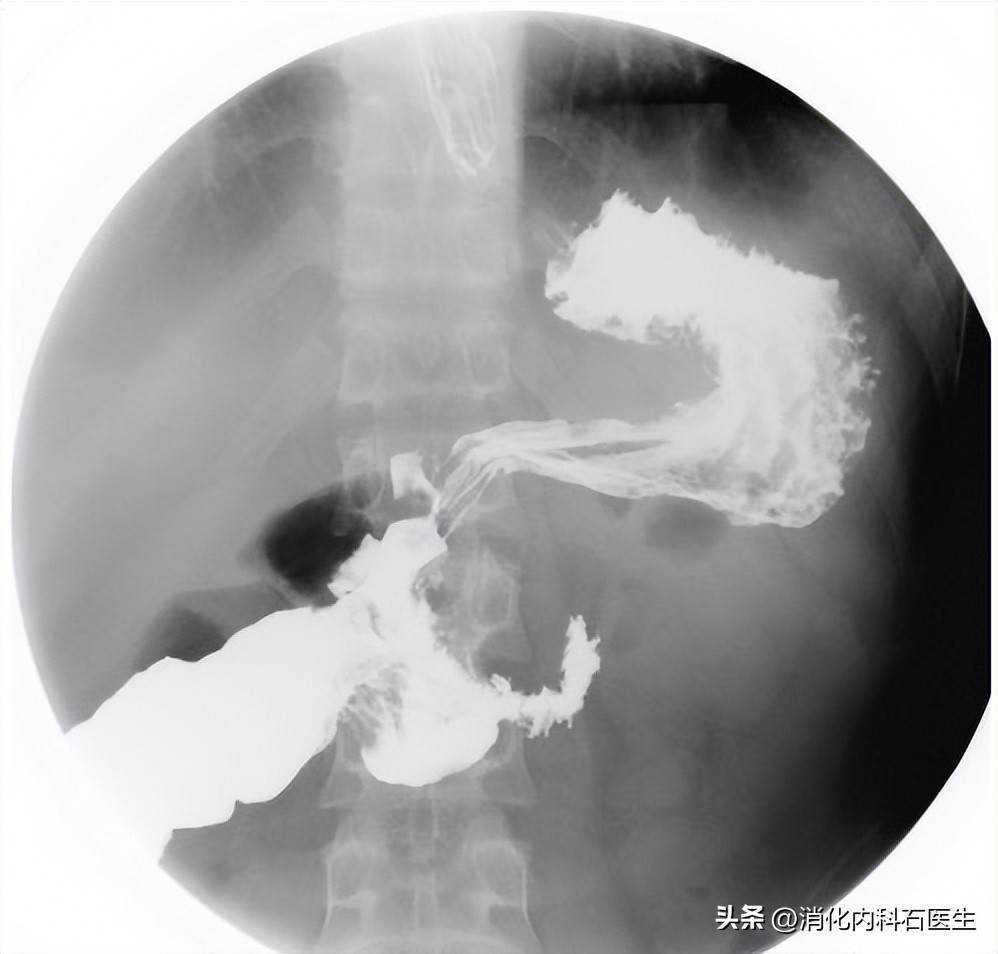

但是有病还得查啊,在医生的强烈建议下,张女士同意做了个钡餐透视。

钡餐透视,真的发现了问题:

胃内有一个巨大的胃石。

上腹部钡餐透视